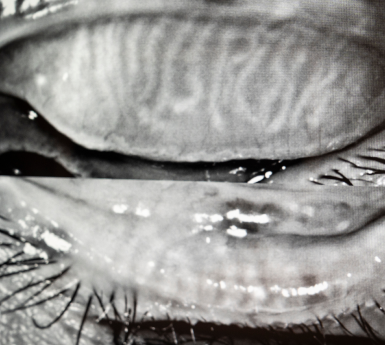

Advanced imaging, meibomography, is needed to directly image the 30-40 glands in your upper and 30-40 glands in the lower lids. Meibomian Gland Dysfunction (MGD) accounts for 86% of dry eye. Often these glands are obstructed but they can also simply produce poor quality oil due to nutrition, medication use, incomplete blinking, or systemic disease. Gland loss, like oral gum loss, can occur if care and maintenance aren’t instituted. We can measure your gland loss and initiate treatment to prevent future loss.